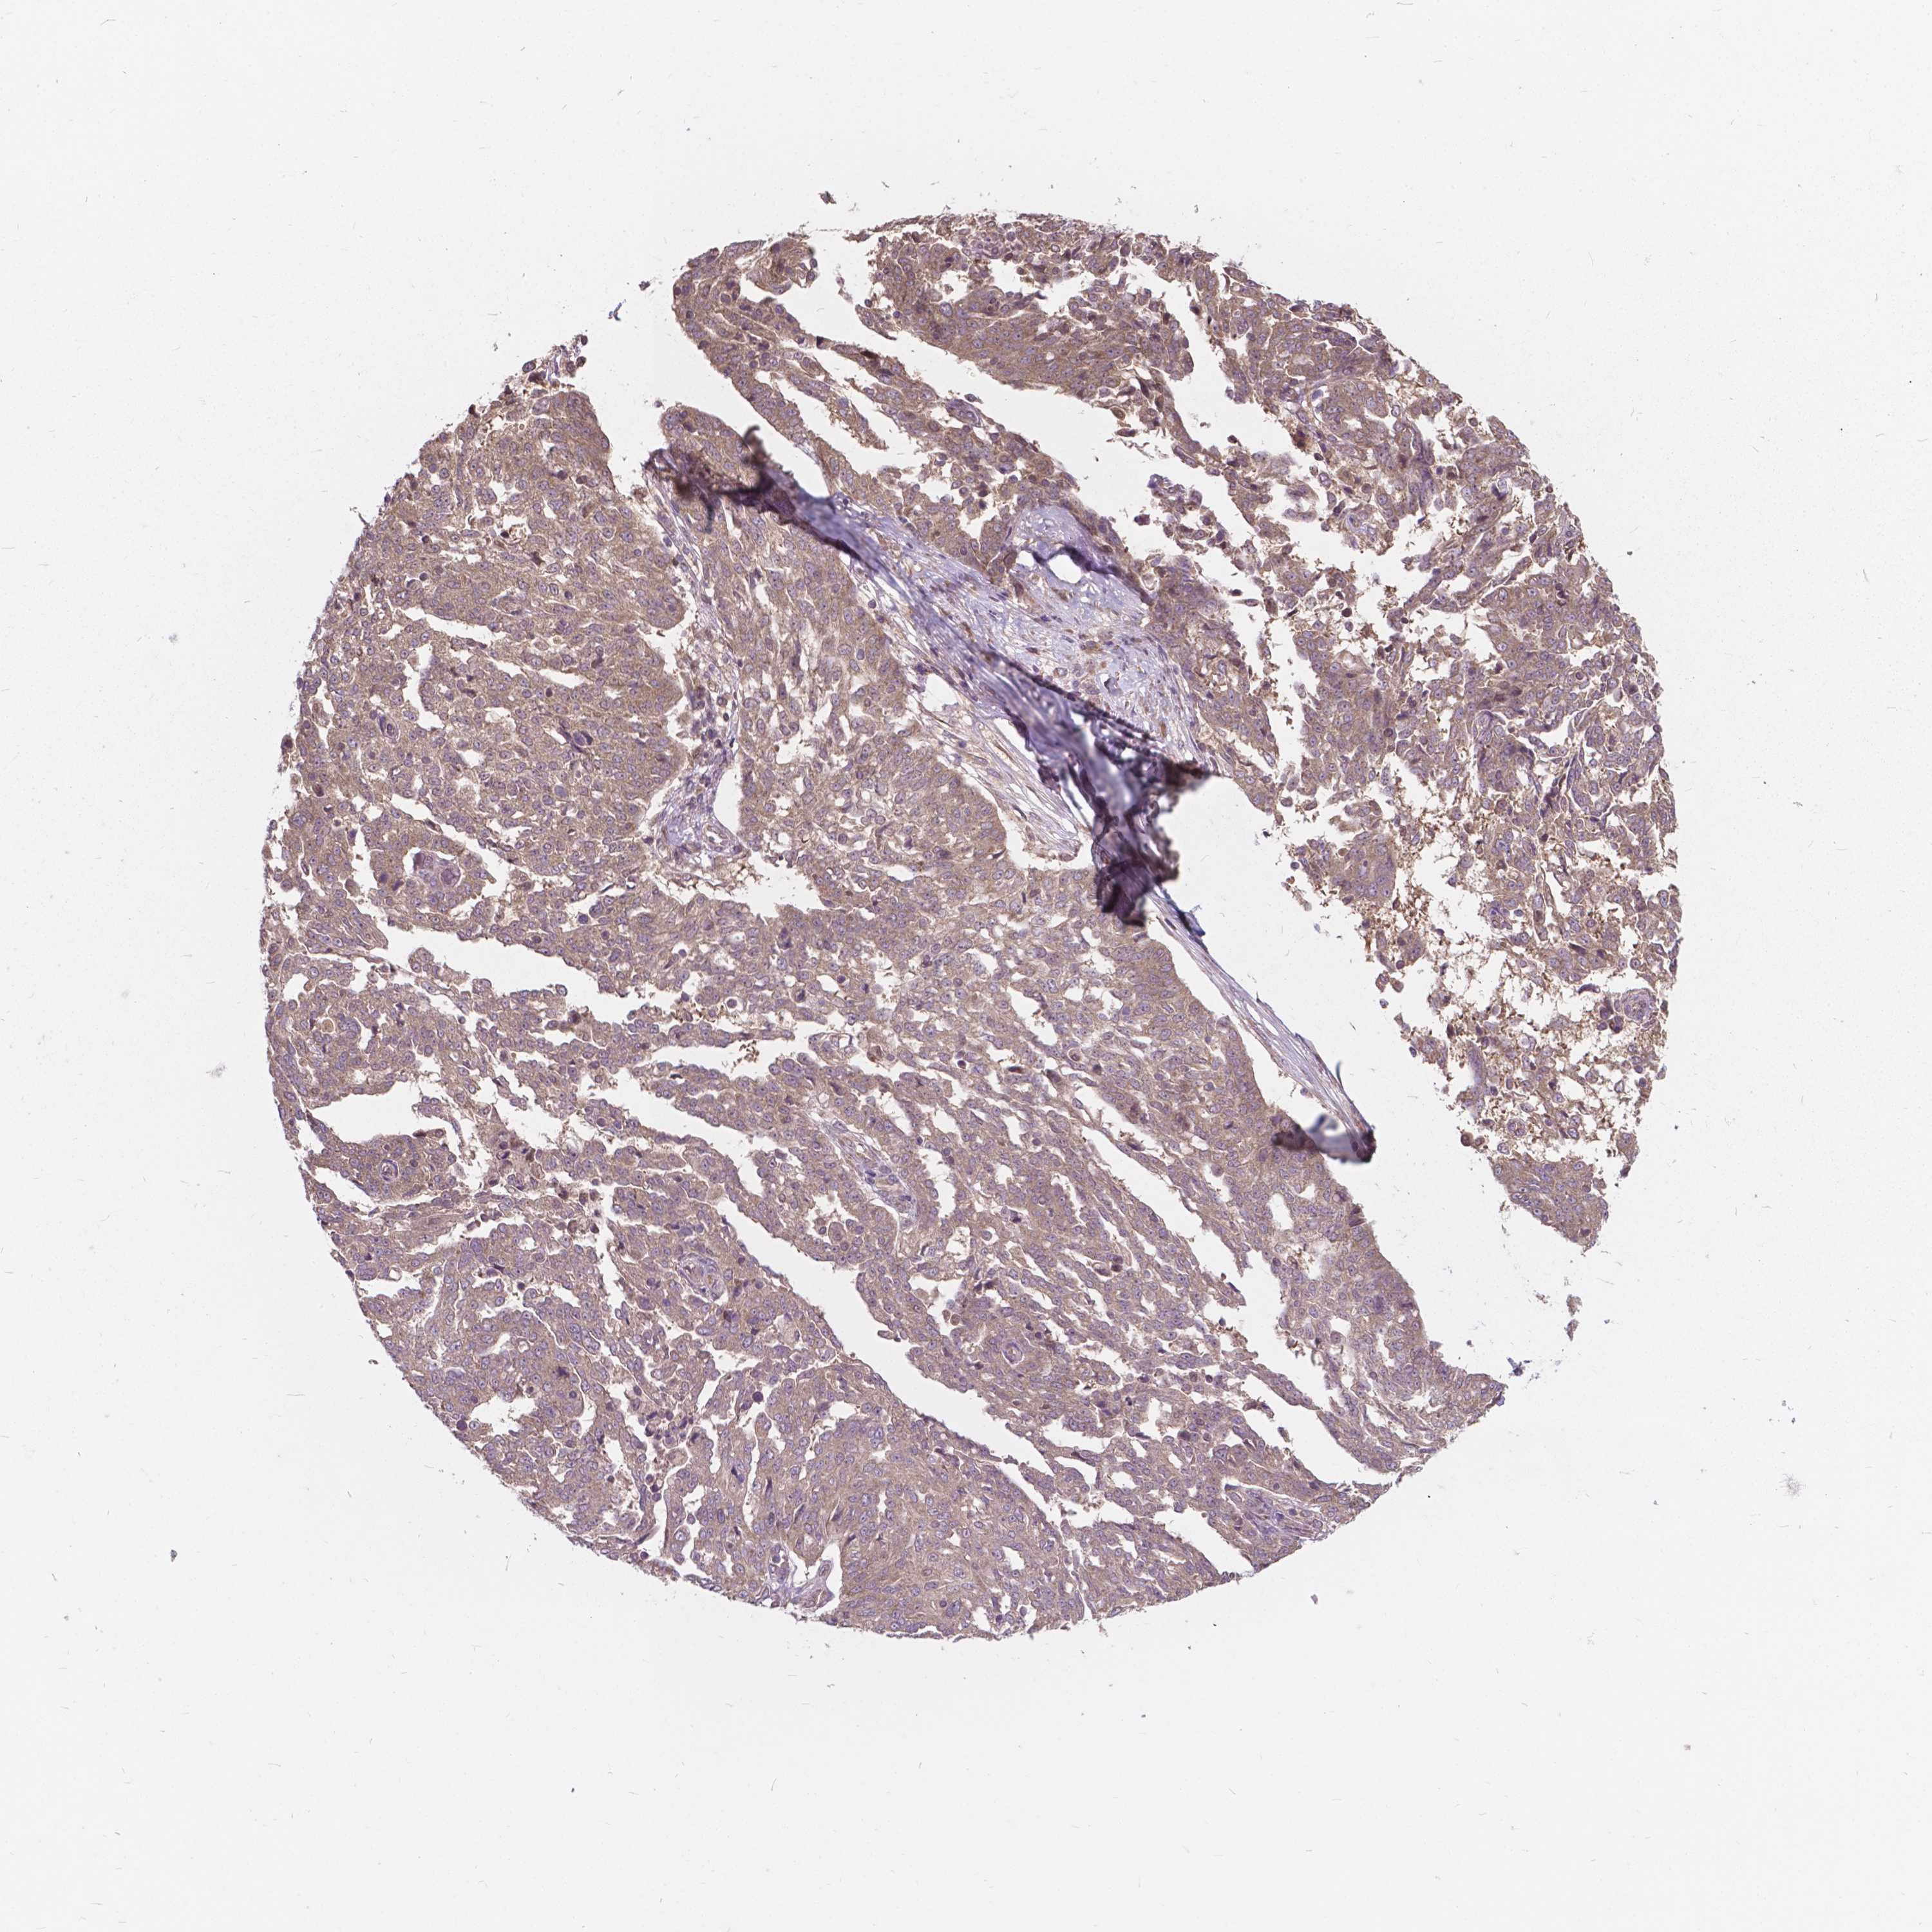

OVARIAN CANCER - Protein expressioni

A mouse-over function shows sample information and annotation data. Click on an image to view it in a full screen mode. Samples can be filtered based on level of antibody staining by selecting one or several of the following categories: high, medium, low and not detected. The assay and annotation is described here.

Note that samples used for immunohistochemistry by the Human Protein Atlas do not correspond to samples in the TCGA dataset.

Antibody stainingi

Antibody staining in the annotated cell types in the current human tissue is reported as not detected, low, medium, or high, based on conventional immunohistochemistry profiling in selected tissues. This score is based on the combination of the staining intensity and fraction of stained cells.

Each image is clickable and will lead to virtual microscopy that enables deeper exploration of all samples and also displays staining intensity scores, fraction scores and subcellular localization as well as patient and tissue information for each sample.

Antibody HPA066872

Staining

High

Medium

Low

Not detected

Intensity

Strong

Moderate

Weak

Negative

Quantity

>75%

75%-25%

<25%

None

Location

Nuclear

Cytoplasmic/membranous

Cytoplasmic/membranous,nuclear

Cystadenocarcinoma, serous, NOS

Cystadenocarcinoma, mucinous, NOS

Carcinoma, endometroid